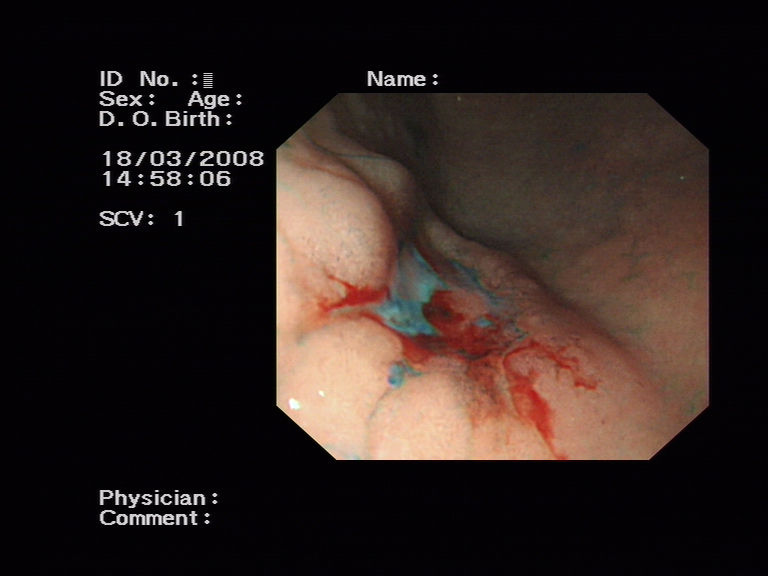

我科利用染色胃镜诊断早期胃癌1例,见附件图片。

病变染色后.bmp